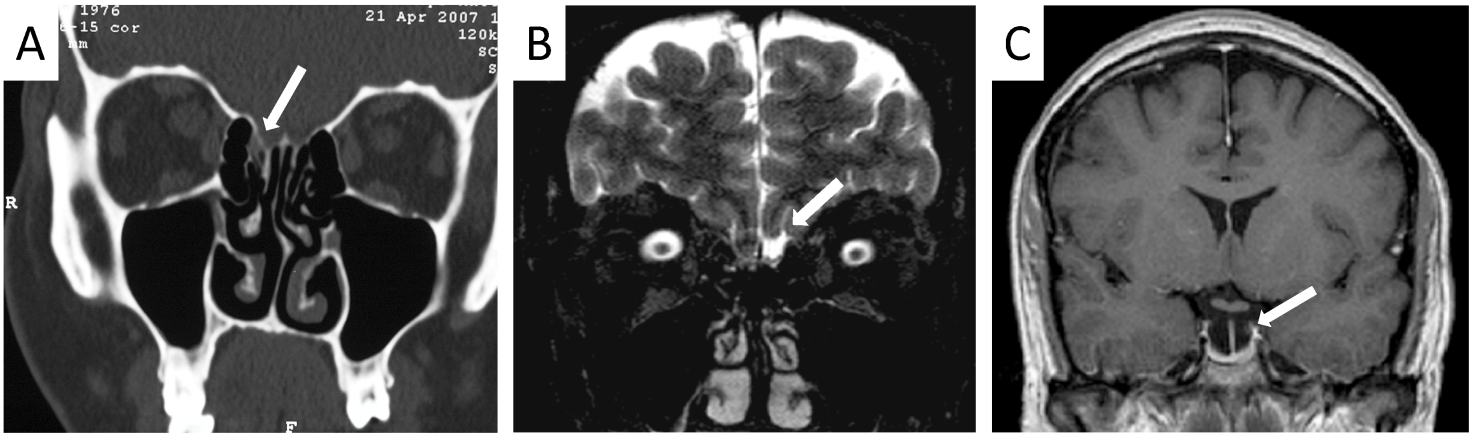

Patients that were diagnosed with nasal rhinoliquorrhea had either already received or immediately received high resolution computed tomography of the skull base and the paranasal sinuses. In five cases (41.6%), a lesion could be identified in the computed tomography (Figure 1 [Fig. 1], Table 2 [Tab. 2]). Furthermore, eight patients received magnet resonance imaging (MRI) with intrathecal application of contrast material (Figure 1B [Fig. 1]; MRIFF cisternography). Out of these eight patients, a lesion could be identified in six cases (75%). In two patients, a meningocele (16.7%) and in one patient (8.3%), an empty sella syndrome was found.

Figure 1: A) CT: CSF-leak of the lamina cribrosa right side. B) MRI: CSF-leak of the lamina cribrosa left side. C) MRI: empty sella syndrome.